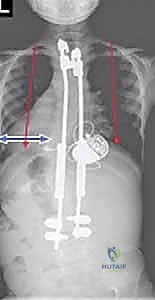

Clinical & Radiographic Imaging